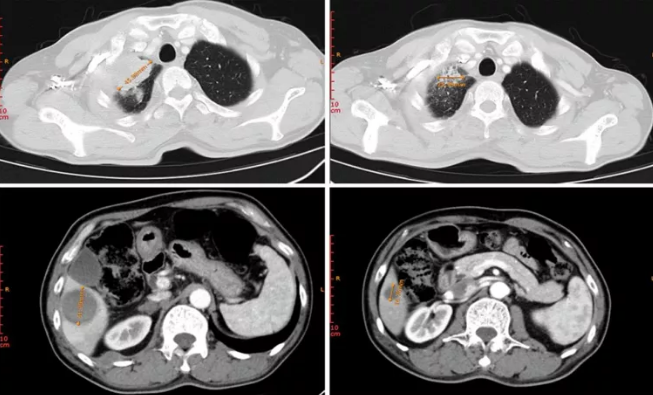

病例1患者为晚期原发性支气管肺癌(腺癌),接受埃克替尼一线治疗超过13个月之久,进展(不存在T790M突变)后入组MRG003针对EGFR阳性晚期NSCLC进行的Ⅱ期临床试验,治疗仅2次(6周),靶病灶直径总和缩小51.1%,疗效评估达PR(图1)。

图1. 治疗前(左上:右肺上叶病灶;左下:肝脏转移病灶)及治疗后(右上:右肺上叶病灶;右下:肝脏转移病灶)病灶变化